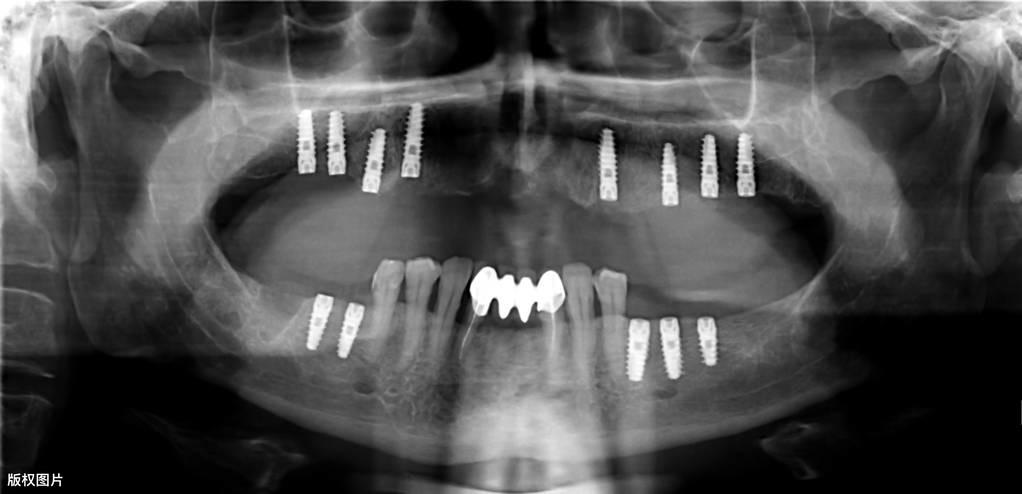

種植牙的一般流程● 術(shù)前檢查:術(shù)前需要拍攝X線片、頜骨CT等,對缺失牙的部位及整個口腔狀況進(jìn)行系統(tǒng)性檢查。符合種植的適應(yīng)癥,排除禁忌癥后,根據(jù)患者的具體情況制定種植調(diào)節(jié)方案,預(yù)約種植手術(shù)時間。

● 垂直方向的骨吸收不超過種植手術(shù)完成時植入在骨內(nèi)部分長度的1/3(采用標(biāo)準(zhǔn)投照方法X光片顯示)。醫(yī)學(xué)教育|網(wǎng)搜集橫行骨吸收不超過1/3, 種植體不松動。

● 放射學(xué)檢查,種植體周圍骨界面無透影區(qū)。